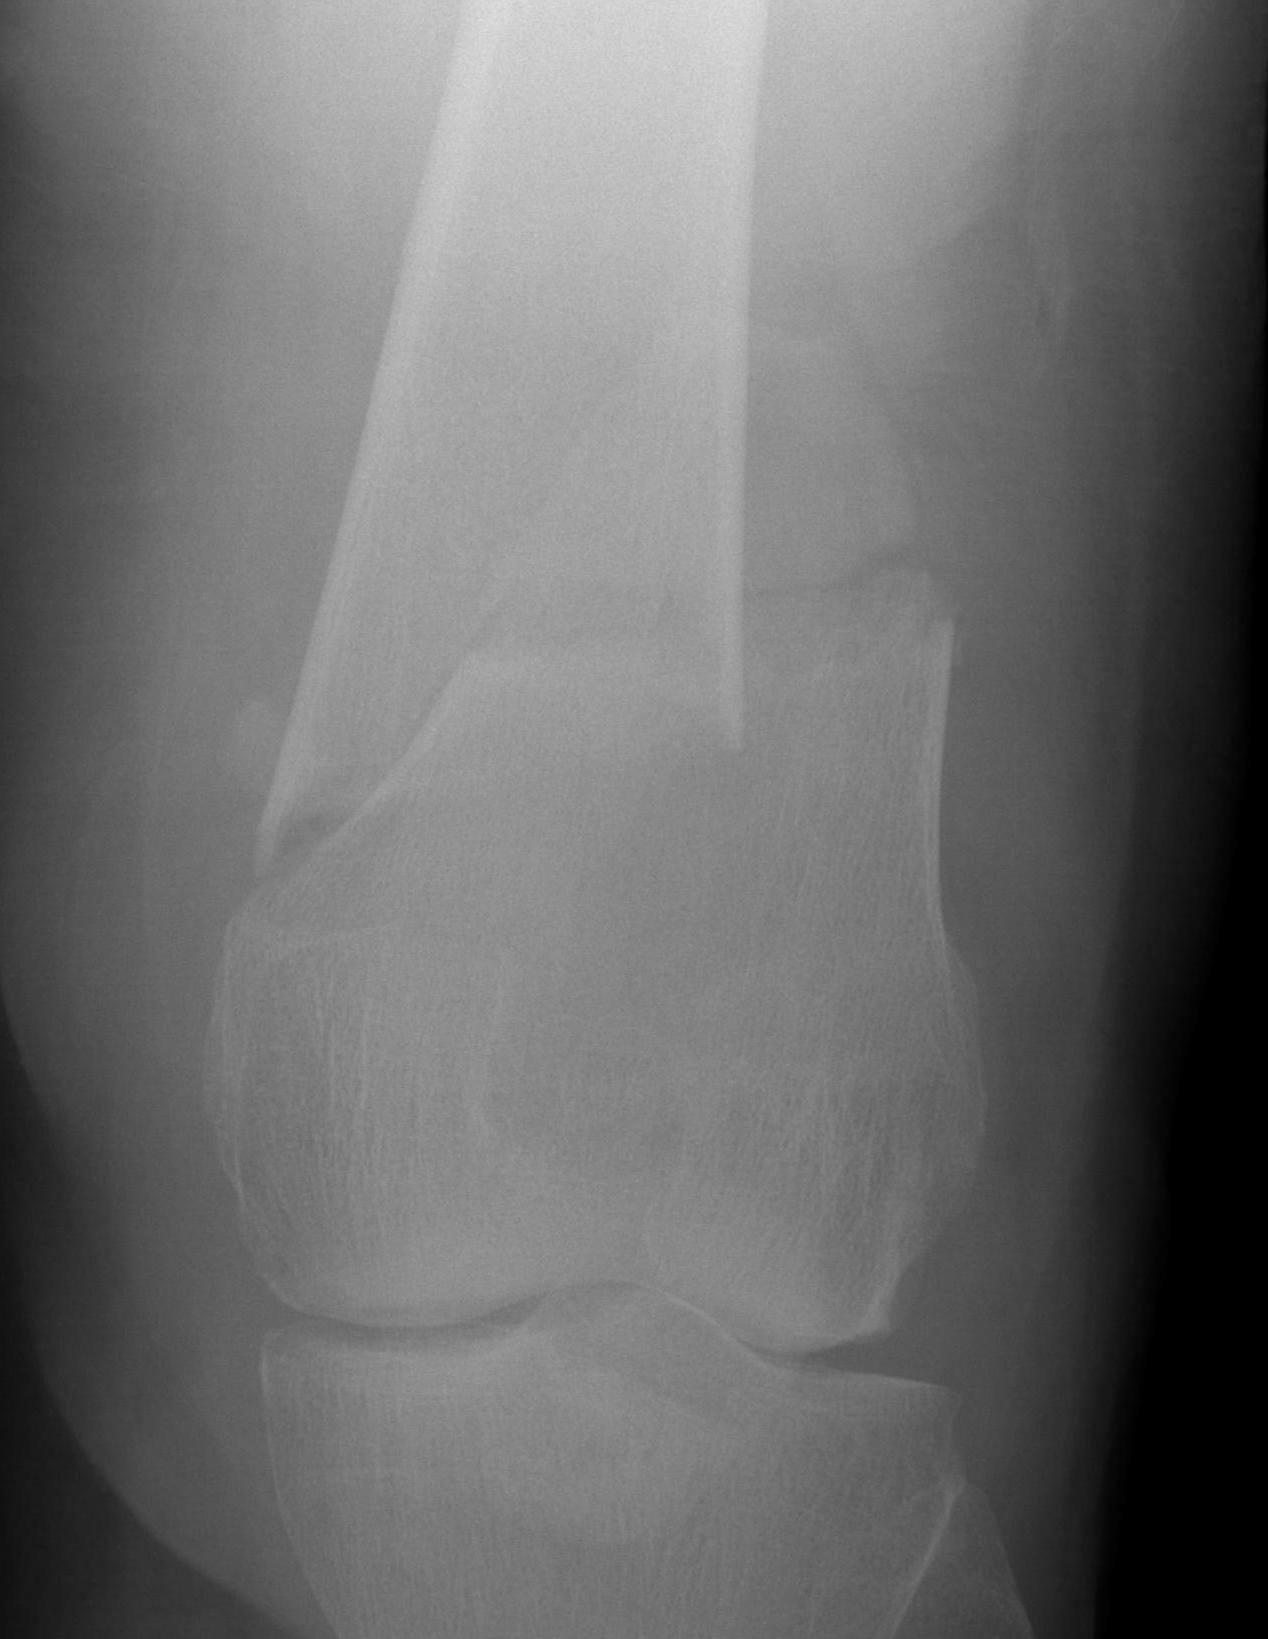

AO Type A: Supracondylar / Extra-condylar

Xray

Options

Lateral plate

Retrograde IM nail